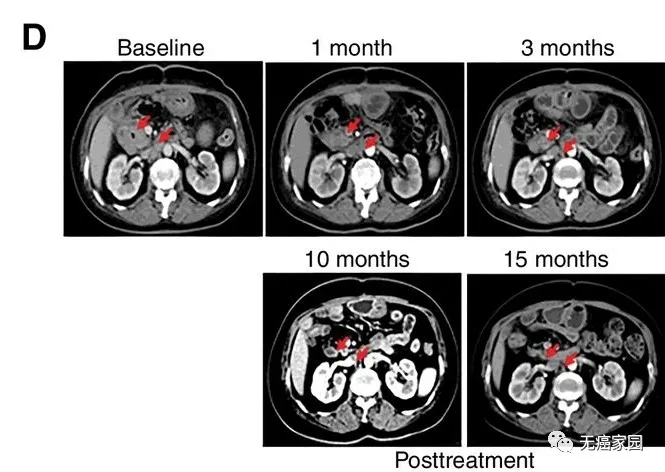

研究结果显示,17例患者可评估,其中1例胆管癌患者的肿瘤完全消失,截止到目前疗效已经保持了22个月,尚未发现疾病复发。10例患者疾病稳定,疗效保持2.5~15.5个月,中位无进展生存期为4个月。

CART-RGFR细胞治疗之前和1、3、10和15个月患者1的CT扫描图像。红色箭头表示原发肿瘤和腹膜后淋巴结转移。在研究中有10例患者在化疗预处理中出现3~4级的副作用,经积极处理均可恢复正常。

这是中国人自主研发的针对实体瘤的CAR-T第一次报道不错的临床疗效。极度恶性的胆管癌患者,首次出现了完全缓解,可喜可贺!